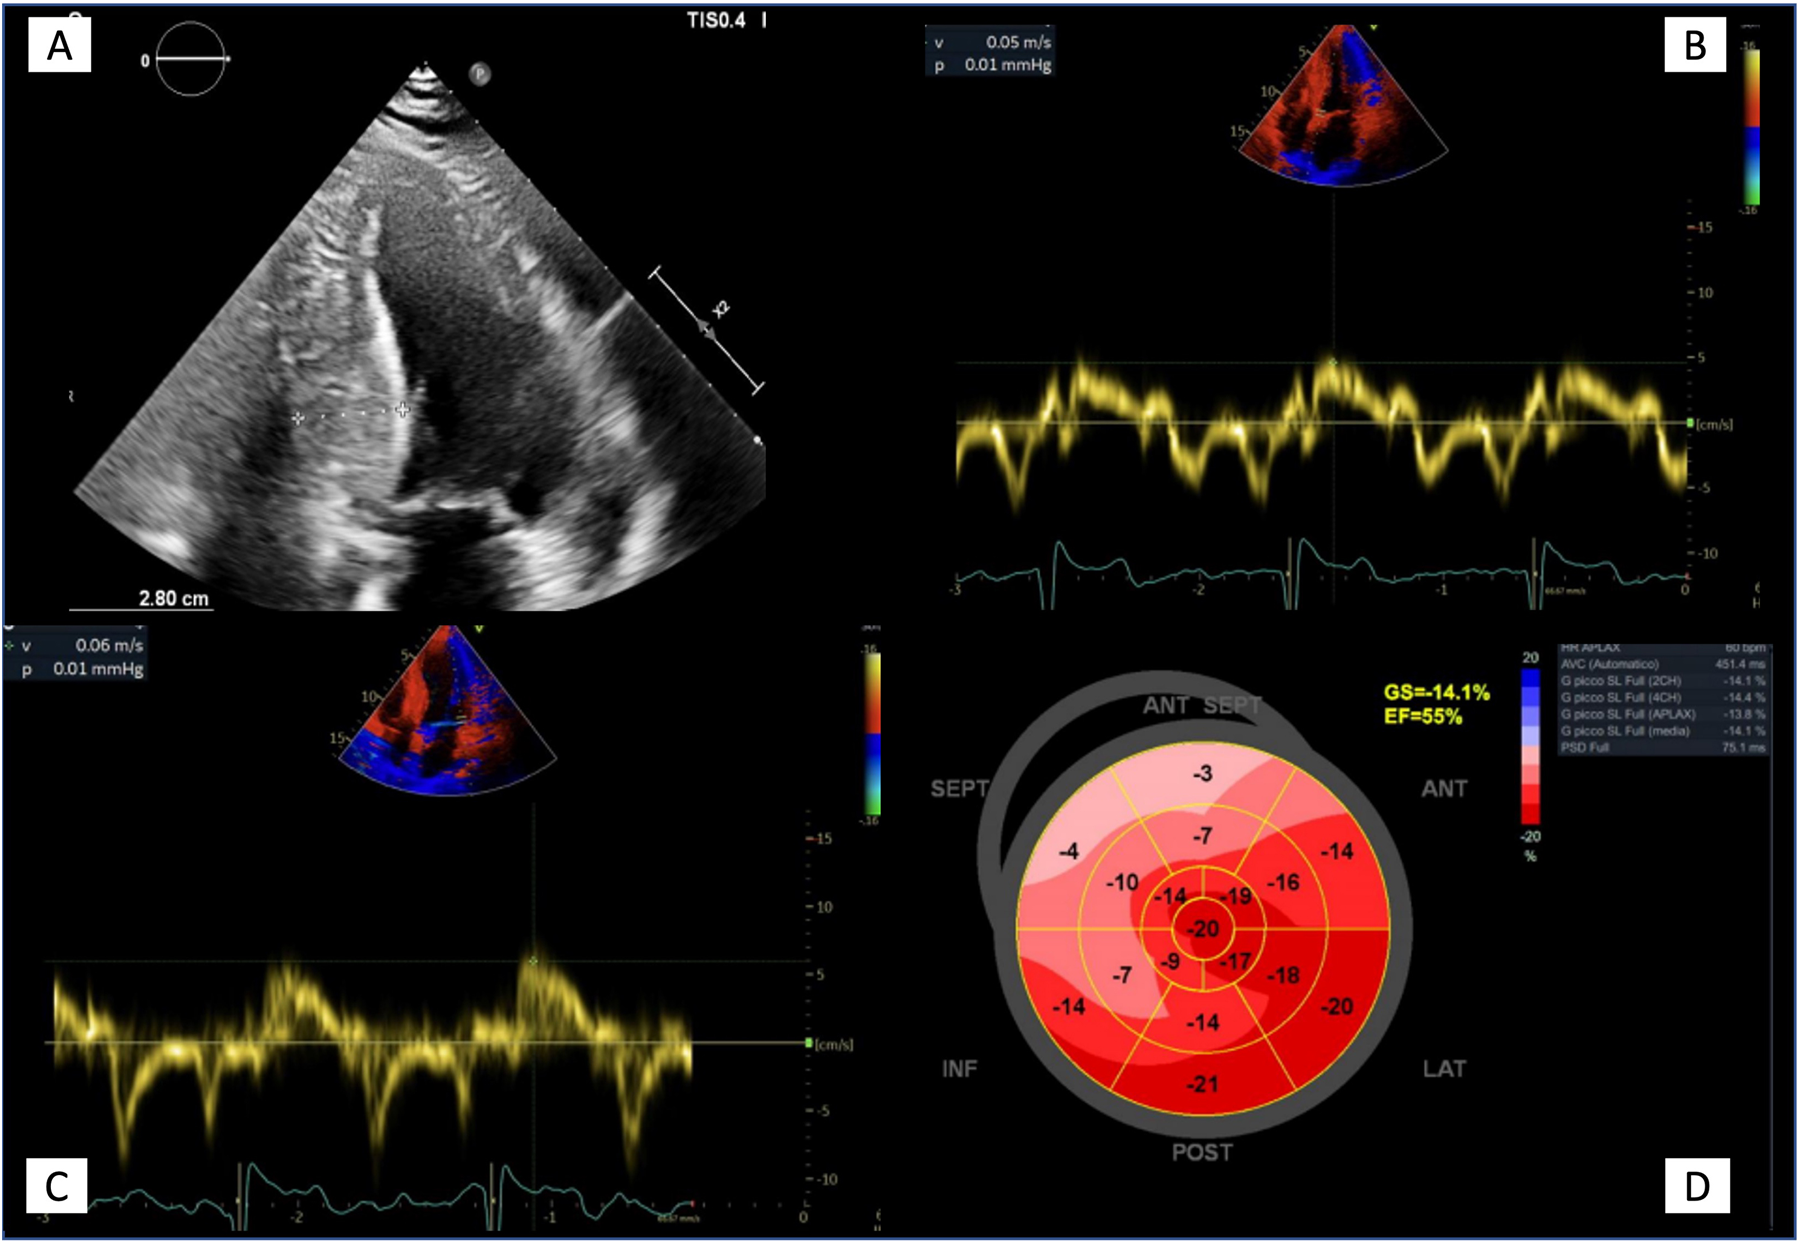

Figure 3. Echocardiographic features in advanced Anderson-Fabry disease cardiomyopathy. (A) Apical four chambers view showing the maximal wall thickness (28 mm) and the typical binary sign; (B, C) Tissue Doppler mitral annular velocities at septal and lateral corners respectively, showing low systolic velocities (5 and 6 cm/s respectively); (D) 2D speckle tracking analysis bull's eye plot, showing reduced LV GLS value (−14.1%).